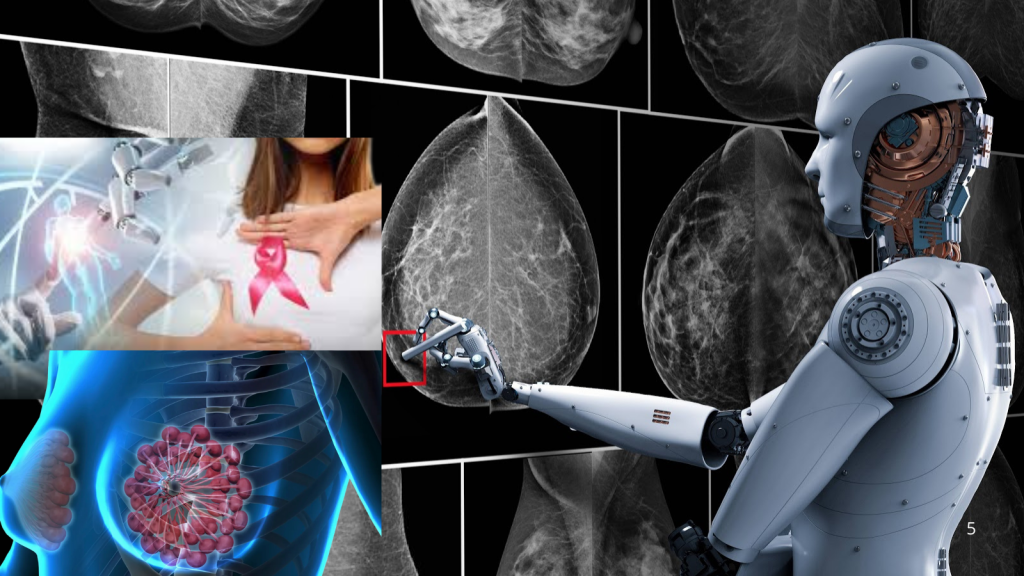

La inteligencia artificial podría transformar la forma en que se detecta el cáncer de mama durante los chequeos rutinarios. Un ensayo clínico sugiere que esta tecnología ayuda a identificar señales difíciles de ver en las mamografías y reduce los casos que se diagnostican entre revisiones médicas, conocidos como “cánceres de intervalo”, que suelen ser más agresivos.

Un estudio realizado en Suecia, con más de 100,000 participantes, encontró que las mamografías asistidas por inteligencia artificial detectaron más casos de cáncer en etapas tempranas y redujeron la aparición de tumores diagnosticados entre evaluaciones. Los resultados fueron publicados el 29 de enero en la revista médica The Lancet.

La investigación incluyó mujeres de entre 40 y 74 años que se realizaron pruebas en cuatro centros médicos entre abril de 2021 y diciembre de 2022. La mitad siguió el proceso tradicional, donde dos radiólogos analizan las imágenes. El resto fue evaluado con un sistema comercial de inteligencia artificial que identificaba zonas sospechosas y definía el nivel de riesgo de cada caso.

El programa asignaba los estudios de bajo riesgo a un solo médico y los de mayor probabilidad a dos especialistas, además de resaltar posibles anomalías en las radiografías. Con este método, se registró una reducción del 12 % en los cánceres de intervalo y una disminución del 16 % en los casos que ya habían invadido tejido sano.

Asimismo, el 81 % de los diagnósticos en el grupo que utilizó inteligencia artificial se detectaron durante los chequeos rutinarios, frente al 74 % en el grupo que siguió el modelo convencional. Investigaciones previas relacionadas con este ensayo también señalan una reducción del 44 % en la carga de trabajo de los radiólogos sin afectar la capacidad de detectar la enfermedad.